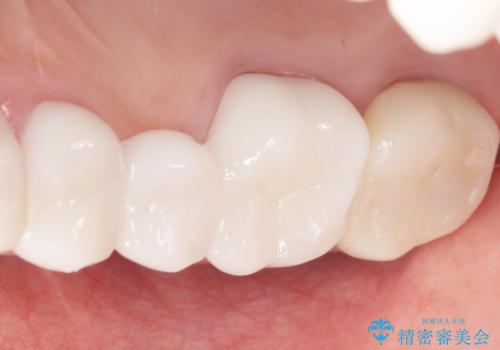

患者様のご希望により、金属を使わないオールセラミックのブリッジによる補綴治療を行いました。

金属の土台も除去し、ファイバーコア(金属を使わない強度のあるしなやかな土台)へやりかえました。

自然な仕上がりと咬み心地に喜んで頂けました。